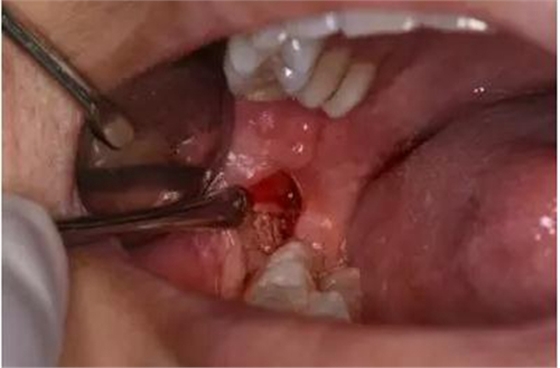

圖7.切開47遠(yuǎn)中齦溝并延長(zhǎng)至磨牙后區(qū)約1cm。

圖9.翻小瓣、用骨膜剝離器輕柔牽拉頰側(cè)齦瓣、暴露48合面

圖10.普通牙挺放置在48牙冠的近中根面與牙槽嵴頂之間,采用推力和挺力,挺松48.